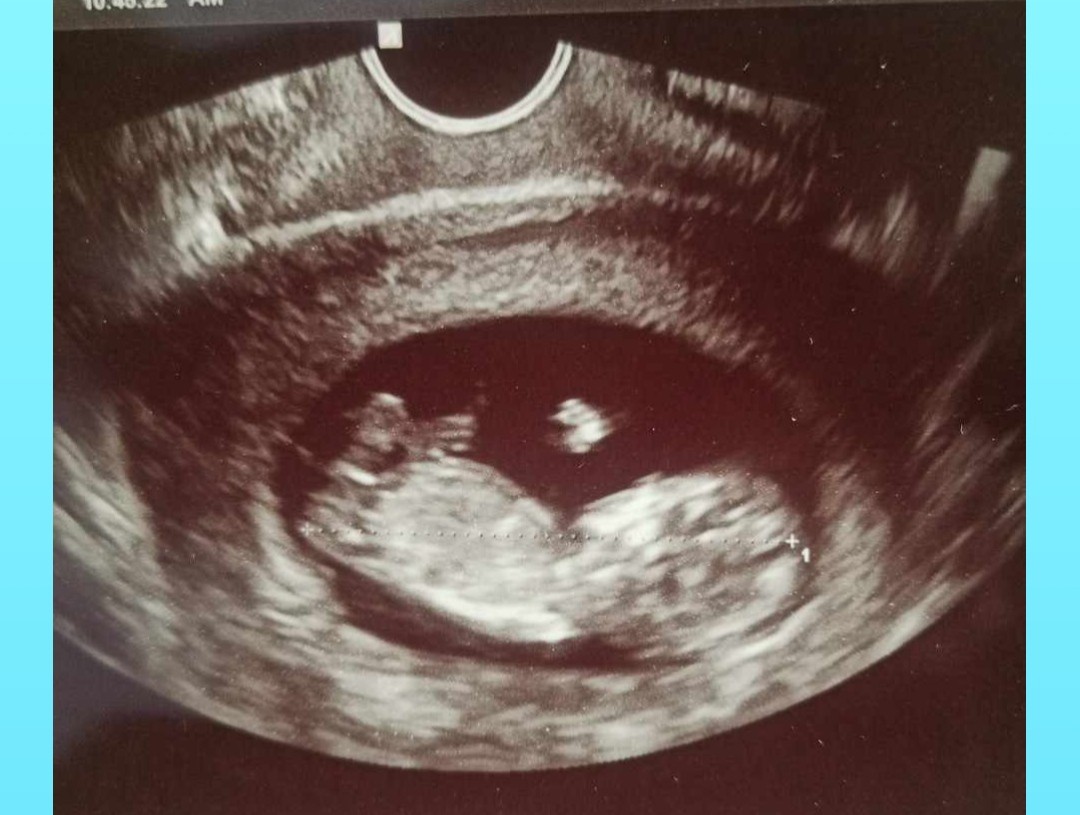

11+6 to za wczesnie na ocenę wyrostka płciowegoDzień dobry. Czy na tych zdjęciach widać już płeć? Jak myślicie ?![]()

ok jak można to usunąć ?11+6 to za wczesnie na ocenę wyrostka płciowegoPS na drugim zdjęciu widnieje Twoje imię i nazwisko.